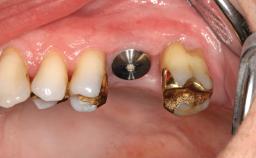

# of Implants | 3 |

Abutment Type | Standard |